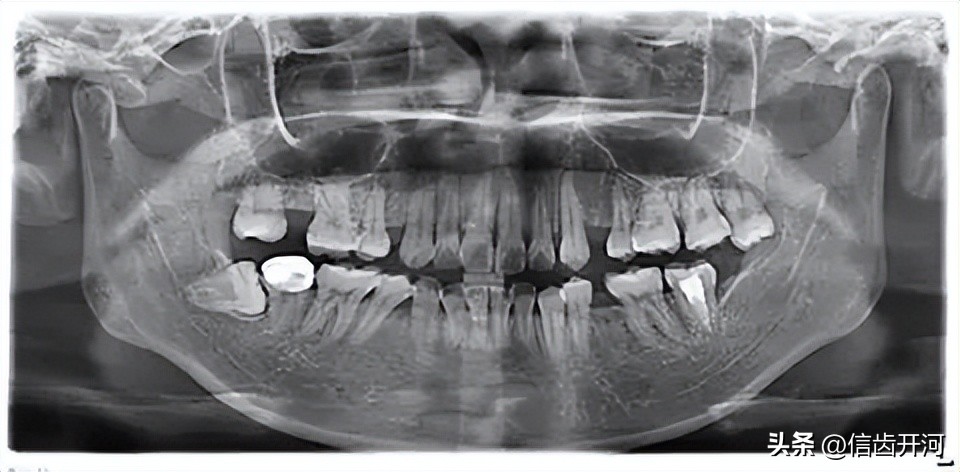

03X线及其他检查

1、X线检查的记录: 要清楚描述异常情况,位置、范围(mm×mm)、边界、形状、密度等。

阻生齿位置:高位阻生或低位阻生;部分阻生或完全阻生;软组织内阻生或骨组织内阻生,与神经管或上颌窦的关系等。

方向:包括近中、远中、垂直、水平、倒置阻生等。